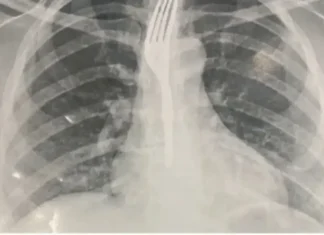

Mulher engole garfo inteiro durante refeição no interior da Bahia

A paciente foi transferida para Vitória da Conquista - Foto: Achei Sudoeste

Um caso inusitado mobilizou equipes médicas no município de Guanambi, na Bahia, na sexta-feira, 26. Durante uma refeição, uma...